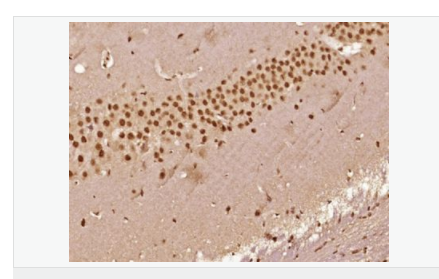

產(chǎn)品應(yīng)用IHC-P=1:100-500 IHC-F=1:100-500 ICC=1:100-500 IF=1:100-500 (石蠟切片需做抗原修復(fù))

細(xì)胞定位細(xì)胞核 細(xì)胞漿